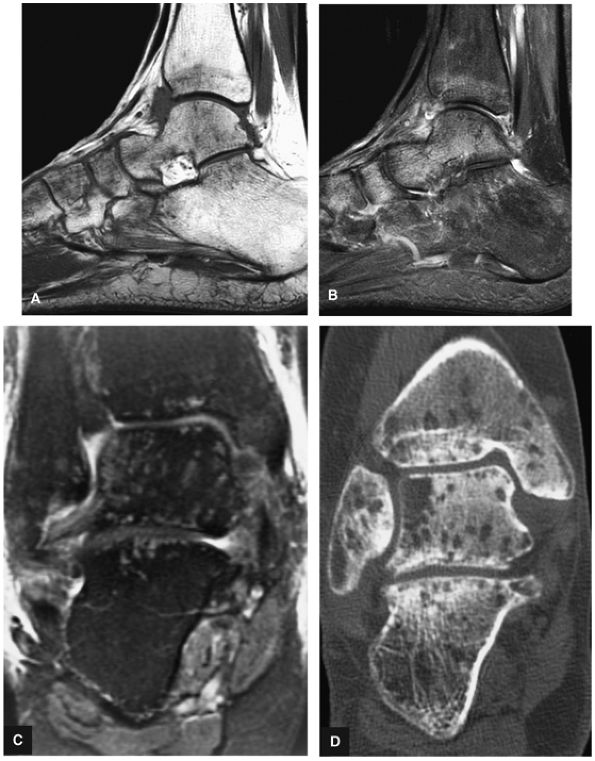

FIGURE 5.94 ● Lateral OLT with intact overlying chondral surface. Subchondral trabecular fracture and adjacent marrow edema are demonstrated on a coronal T1-weighted image (A). Mid-lateral talar dome location is shown with a cross-sectional area of reactive marrow edema. The edema associated with OLT should not be misinterpreted and result in overestimation of the area of trabecular bone involved. Coronal T1-weighted image. (B) Coronal FS PD FSE image. (C) Axial FS PD FSE image. (D) Color illustration with the capsule cut and the tibia and fibula reflected. Compression-type OLT corresponding with an area of subchondral trabecular compression in a stage I lesion.

FIGURE 5.96 ● Stage II (IIA) OLT of the medial talar dome with formation of a subchondral cyst and anterior communication with an injured chondral surface. (A) Coronal color graphic of medial OLT. (B) Coronal T1-weighted image. (C) Coronal FS PD FSE image. (D) Axial FS PD FSE image.